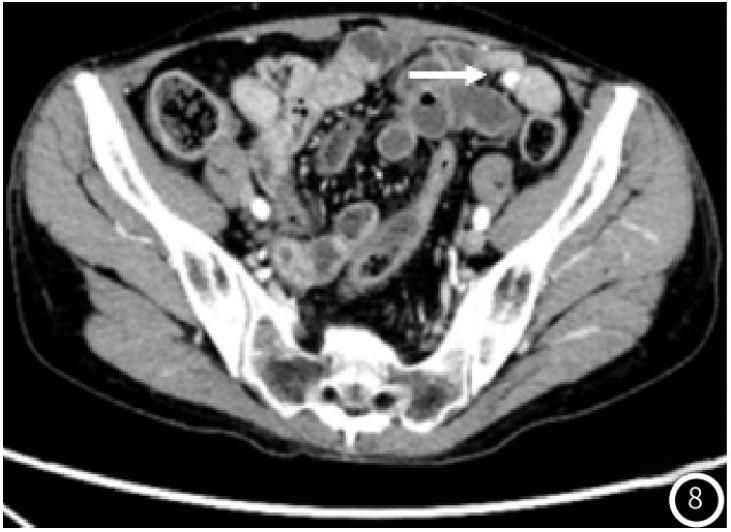

示胰头类圆形低密度结节,大小约14mm×12mm,增强扫描动脉期结节明显均匀强化(图1),强化程度高于正常胰腺实质,静脉期强化减低,边界清;术后4年常规胸腹部CT

图8 盆腔病灶较前大致相仿,位于肠系膜之间,局部与肠管边界不清(白箭头);